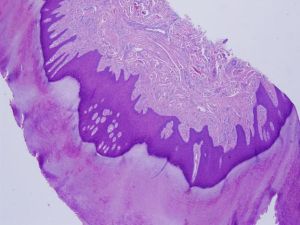

皮脂腺痣的病理變化因病史長短而異在嬰兒和童年,病史中皮脂腺發育不良,不能辨認出大汗腺。表皮輕度增生可見小毛囊及未分化的上皮細胞索條或胚芽。到青年發育期皮損中可見大量成熟或近於成熟的皮脂腺其上方的表皮往往呈乳頭瘤樣增生,可見棘層肥厚。在皮脂腺小葉下方,可見異位的大汗腺。在老年患者的皮損中,表皮多呈疣狀增生,有時可見皮脂腺呈腫瘤樣增生。

組織病理檢查可見表皮過度角化,棘層肥厚;核心部膠原纖維交織成束,垂直排列;彈力纖維細、少,毛細血管豐富。